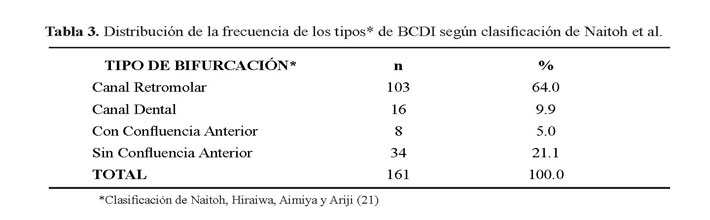

En la tabla 3 se describe la distribución de la frecuencia del tipo de BCDI donde se encontraron 103 casos del tipo canal retromolar (Figura 2, figura 3 y figura 4); no se encontró ningún caso con el tipo de bifurcación canal bucal-lingual.

En conclusión se evidenció que la frecuencia de la BCDI fue del 10,75% (161 casos). Se encontró mayor frecuencia en la quinta década de vida, no hubo diferencia estadísticamente significativa entre el sexo femenino y masculino (p=0.49). La distribución de la BCDI evidenció que el tipo Canal retromolar representó el 64% (103 casos), seguido del tipo Canal sin confluencia anterior con 21.1% (34 casos) y minoritariamente el Canal dental y Canal con confluencia anterior con un 9.9% (16 casos) y 5% (8 casos) respectivamente. No se encontraron casos del tipo canal bucal - lingual.